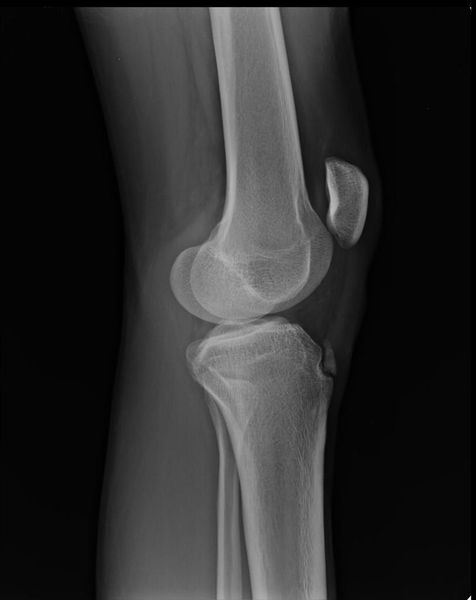

Рентгенограмма при болезни Фонга (синдроме ногтя-надколенника)

б) Визуализация:

1. Общая характеристика:

• Лучший диагностический критерий:

о Рога подвздошных костей являются патогномоничными

2. Рекомендации по визуализации:

• Лучший метод визуализации:

о Для постановки диагноза достаточно рентгенографии вместе с клиническими признаками

(Слева) Рентгенография таза в ПЗ проекции: визуализируются отдельные «рога» подвздошных костей. Эти рога относительно небольшие. Также обратите внимание на широкие горизонтальные вертлужные впадины, которые визуализируются при большом количестве скелетных дисплазий.

(Справа) При рентгенографии в аксиальной проекции определяются характерные диспластические изменения надколенника. Патологические изменения асимметричные, более выражены в левом коленном суставе. Слева отмечается уплощение латерального мыщелка бедренной кости, а также увеличение медиального мыщелка. Также определяются изменения, характерные для раннего остеоартрита.

3. Рентгенография при болезни Фонга (синдроме ногтя-надколенника):

• Рога подвздошных костей:

о Симметричные

о Отмечается в 80% случаев

о Проецируются кзади и латерально от центра подвздошной кости

о Пальпируемые

о Бессимптомные

• Отсутствие/гипоплазия надколенника:

о Асимметрично

о Верхнелатеральное смещение

о Колено выглядит уплощенным

о Чрезмерный рост медиального мыщелка бедренной кости

о Гипоплазия латерального мыщелка бедренной кости

о Увеличение бугорка большеберцовой кости